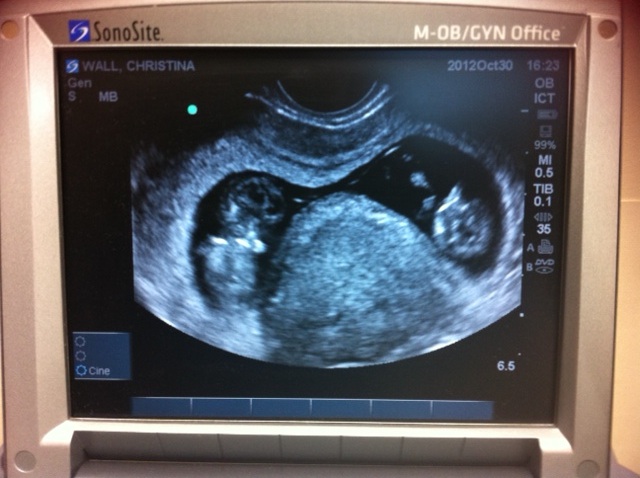

And here's pic #2 at 10w4d. After the second doc came in and confirmed the twin pregnancy and then left, I asked the the ob if she could do another quick ultrasound to print us a picture...I needed a picture of this to look at when I find myself still in disbelief.